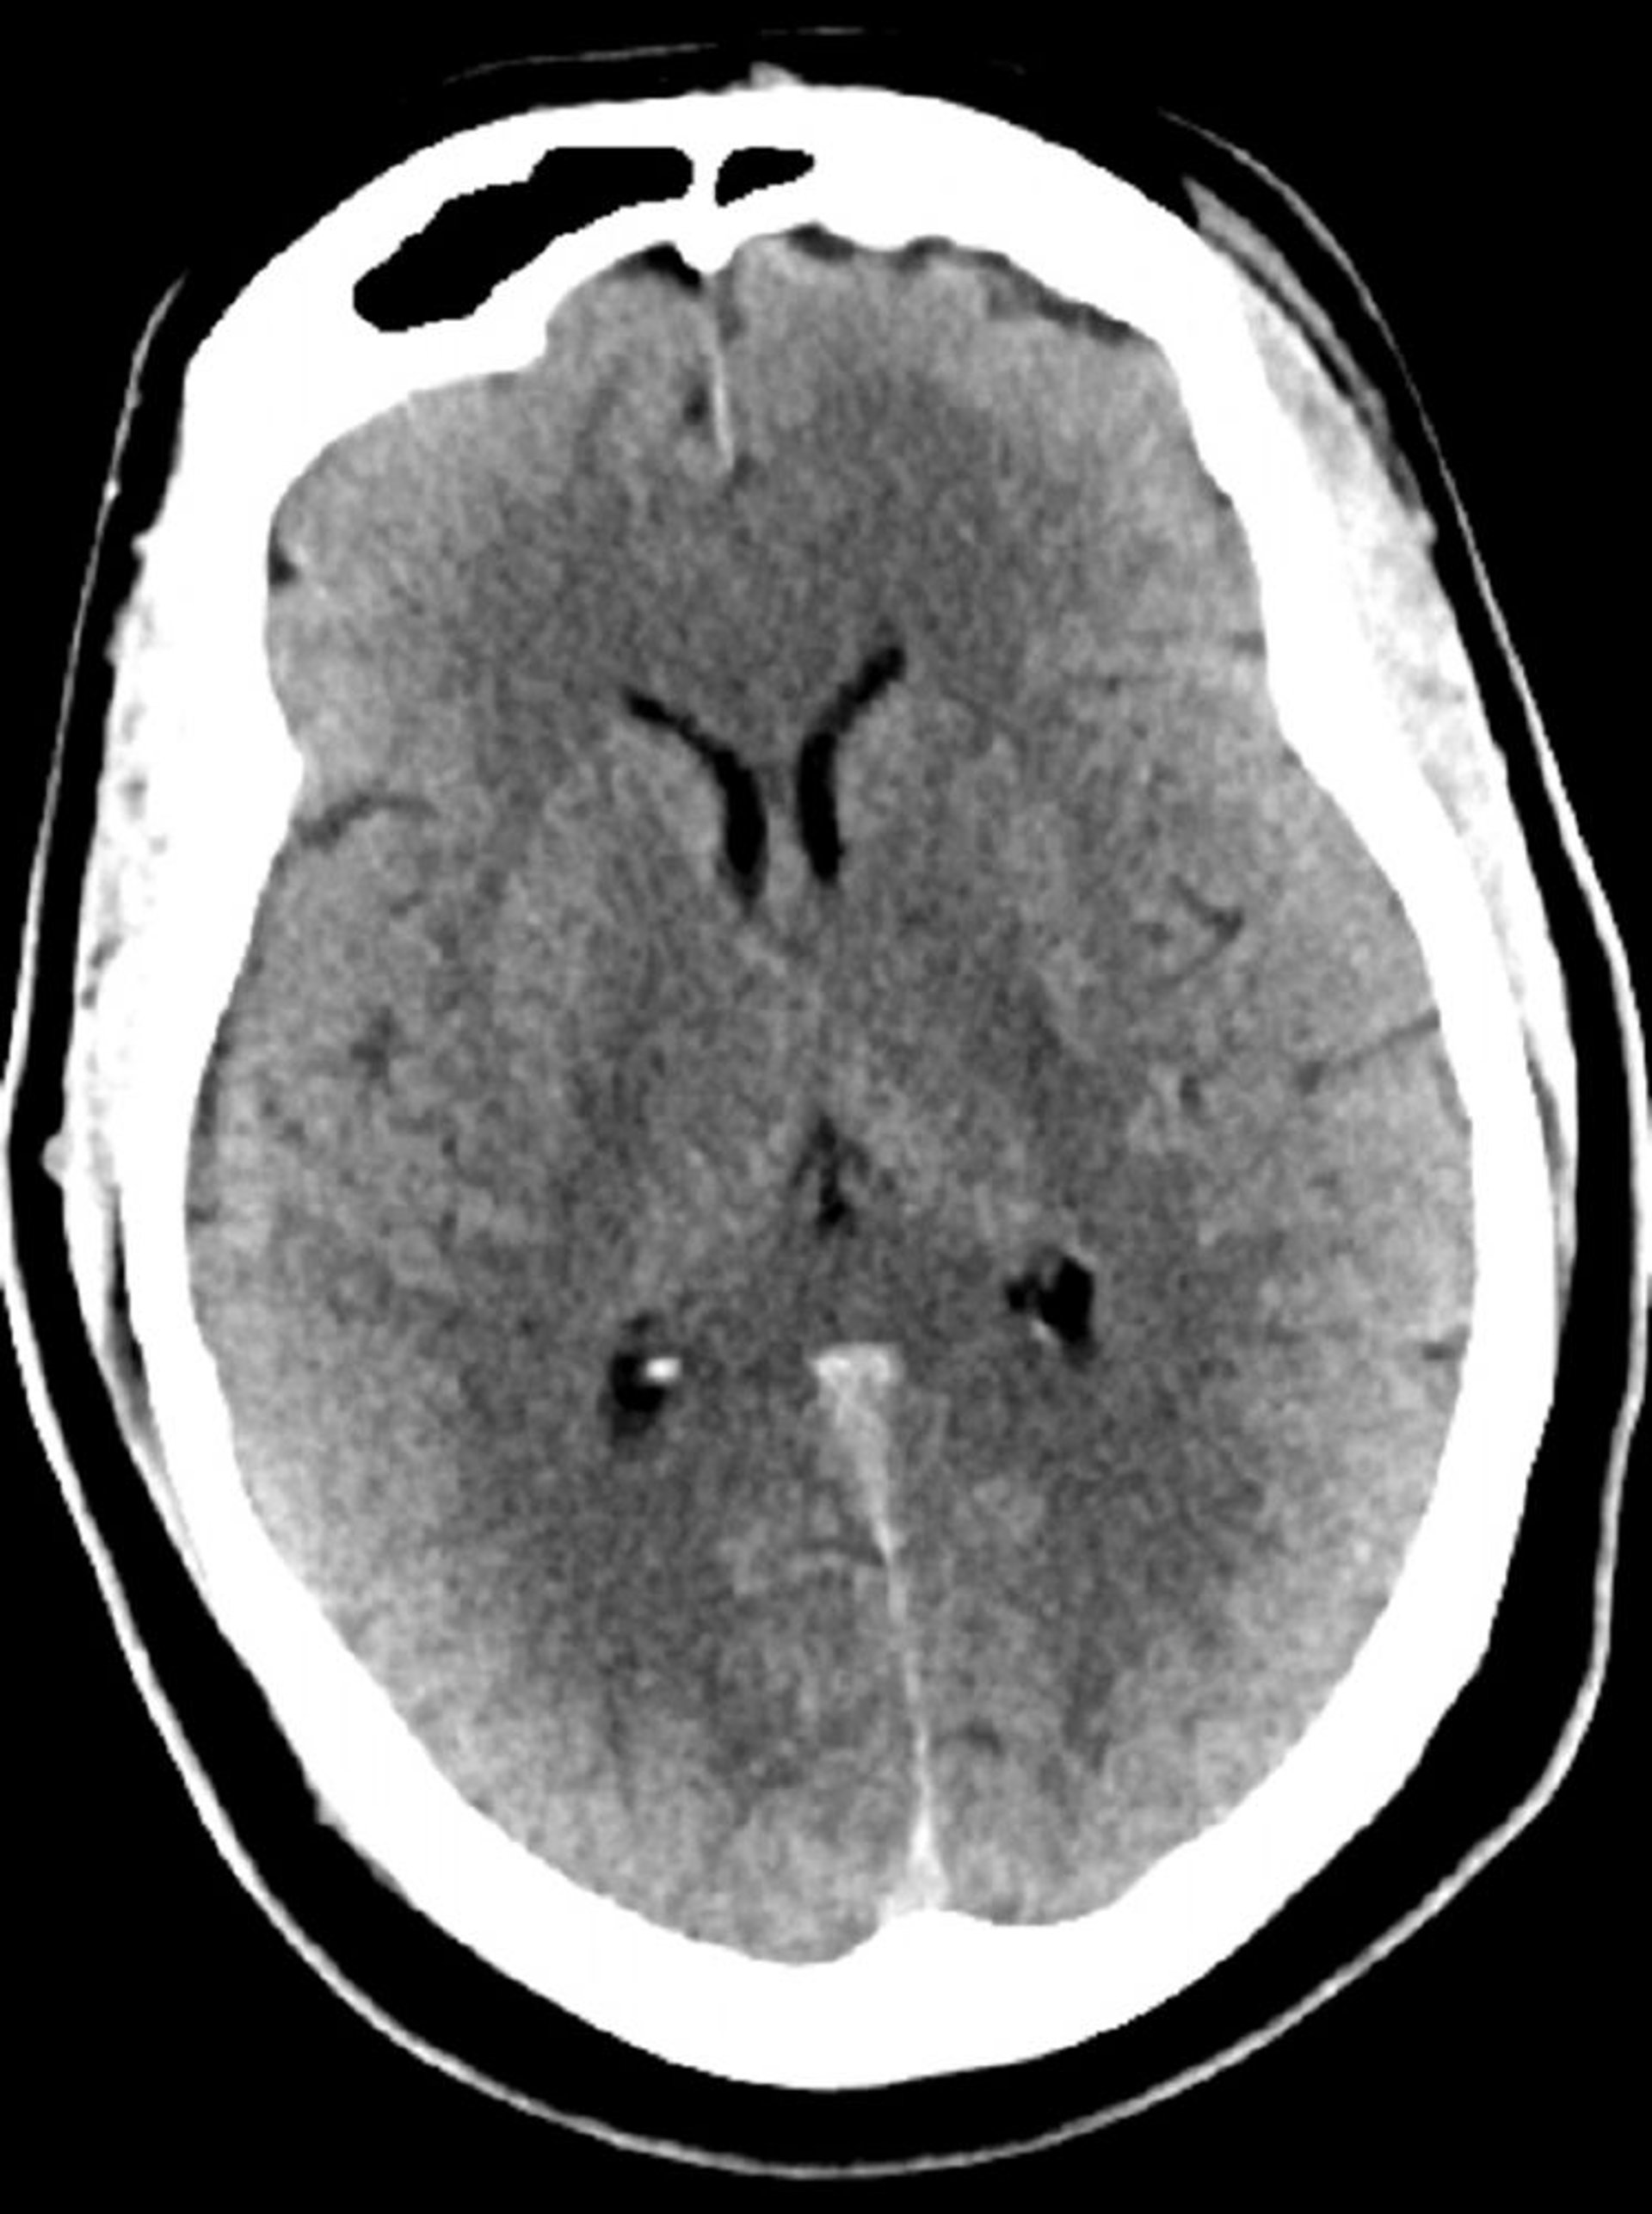

Normal Head CT Scan (Adult, Age 30) – Slide 5

This image is a normal CT scan of the head of a young adult aged 30. There is no intra- or extra-axial fluid or hemorrhage. Grey-white differentiation is preserved. Ventricular size and sulcal pattern are normal.